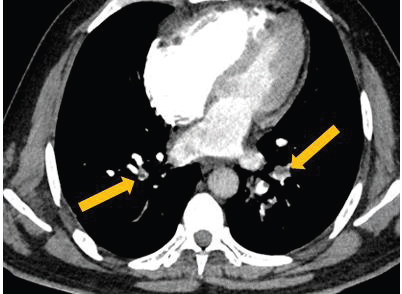

Figure 3:CT pulmonary angiography (CTPA) axial images demonstrate

intraluminal thrombi within the interlobar and segmental branches of

both lungs, consistent with bilateral pulmonary embolism. The total

modified Wells score is 3 (≤4; PE unlikely); however, the age-adjusted

D-dimer level is elevated at 1250 (positive), supporting the diagnosis in

correlation with imaging findings.